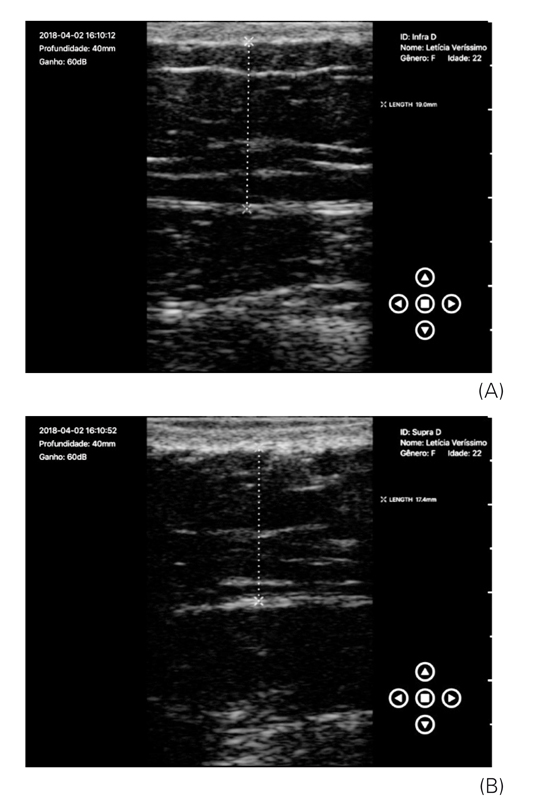

Verificou-se que, no momento inicial nas avaliações das medidas supra e infraumbilical, já existia uma diferença, fato que dificultou a interpretação dos resultados na avaliação final, quando também se observou uma diferença entre as zonas supra e infraumbilical esquerda. Mas ao analisar as imagens de ultrassonografia individualmente, é possível perceber a diferença entre as regiões tratadas e controle, conforme demonstra as Figuras 3A e 3B (análises ultrassonográficas da região infra e supraumbilical esquerda antes do tratamento), Figuras 4A e 4B (análises ultrassonográficas da região infra e supraumbilical direita, controle), Figuras 5A e 5B (análises ultrassonográficas da região infra e supraumbilical esquerda após tratamento) e Figuras 6A e 6B (análises ultrassonográficas da região infra e supraumbilical direita após tratamento, controle).

(A) Análise ultrassonográfica da região infraumbilical direita antes do tratamento, lado controle, 1,90 cm; (B) Análise ultrassonográfica da região supraumbilical direita antes do tratamento, lado controle, 1,74 cm

Os autores.

Por meio das imagens de ultrassonografia demonstradas nas Figuras 3 e 5 e dos dados contidos na Tabela 2, verificou-se que a região tratada teve uma redução importante, comparada com a do lado controle, de 0,6 cm na região infraumbilical e 0,15 cm na região supraumbilical. Do total da amostra, 21 mulheres apresentaram esse comportamento, assim a diferença sempre foi mais acentuada na região infraumbilical, na qual o aplicador da TOC foi utilizado de forma estacionária. Mas no lado controle, percebeu-se que a região infraumbilical não se alterou após o período de quatro semanas e na região supraumbilical a redução foi 0,14 cm, em uma voluntária. Em seis participantes, a região supraumbilical não apresentou redução. Não foram feitas análises em quatro mulheres, pois estas não realizaram o exame final. A análise foi feita pela avaliação do ultrassonografista.